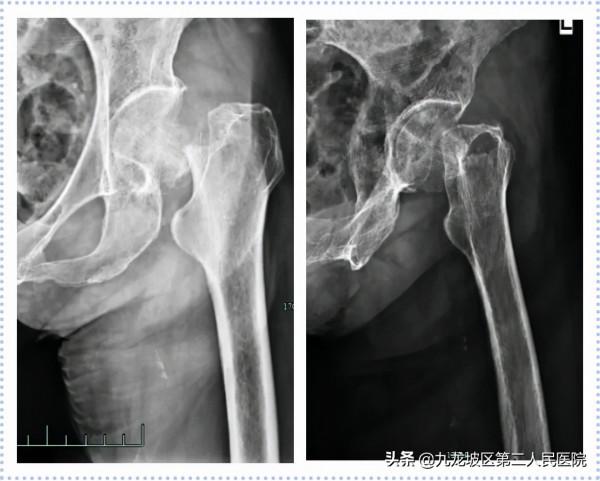

(2)股骨近端聯合加壓髓內釘內固定術(InterTan)

56歲男性,因“車禍致左髖部疼痛伴功能障礙2+小時”入院。診斷為“左股骨粗隆間粉碎性骨折(EvansⅠd型)”。2021年06月02日在我院骨科行左股骨粗隆間骨折閉合復位內固定術(InterTan)。